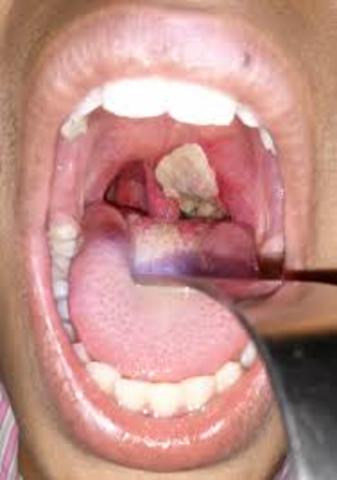

• Diphtheria

Diphtheria

A highly contagious bacterial disease causing inflammation of the mucous membranes, formation of a false membrane in the throat that hinders breathing and swallowing.